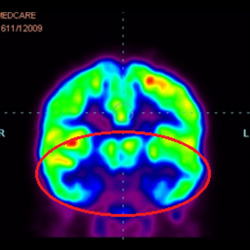

細胞治療前 PET CT 掃描顯示神經(jīng)組織中的藍/黑色區域,表明腦癱引起的大腦損傷。

腦癱細胞療法, 腦癱治療

細胞治療后,藍色和黑色區域減少,并且看到更活躍的區域。這表明損傷減少并改善了大腦功能。